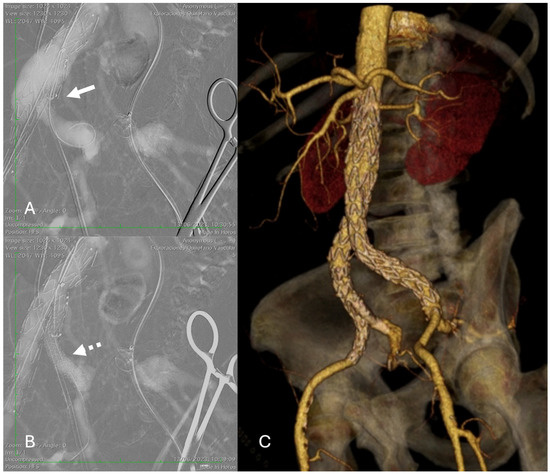

Reverse-Wire TEVAR for Subacute Type B Aortic Dissection with Severe True-Lumen Collapse: A Case Report

Type B aortic dissection (TBAD) requires management tailored to the disease phase and clinical presentation, with the subacute period representing a favorable window for endovascular intervention due to improved procedural safety and remodeling potential. We report the case of a 38-year-old male with [...] Read more.

Type B aortic dissection (TBAD) requires management tailored to the disease phase and clinical presentation, with the subacute period representing a favorable window for endovascular intervention due to improved procedural safety and remodeling potential. We report the case of a 38-year-old male with hypertension, dyslipidemia, and bicuspid aortic valve disease who presented one month after symptom onset with persistent chest pain and progressive bilateral lower-limb numbness. Clinical examination suggested early spinal cord ischemia, while laboratory tests demonstrated acute hepatic and renal dysfunction. CT angiography revealed a subacute TBAD with a markedly expanded false lumen and near-complete compression of the true lumen, resulting in visceral, renal, and potential spinal malperfusion. Given the high-risk anatomy and evolving organ dysfunction, a staged hybrid strategy was undertaken. A left carotid–subclavian bypass was performed to secure proximal landing for endovascular repair, followed the next day by thoracic endovascular aortic repair (TEVAR) using two thoracic stent grafts. Postoperative recovery was favorable, with rapid resolution of neurological symptoms and normalization of hepatic and renal parameters, allowing discharge on postoperative day seven. This case underscores the importance of early recognition of malperfusion and timely hybrid intervention in subacute TBAD with severely compressed true lumen, demonstrating excellent early clinical outcomes. Full article